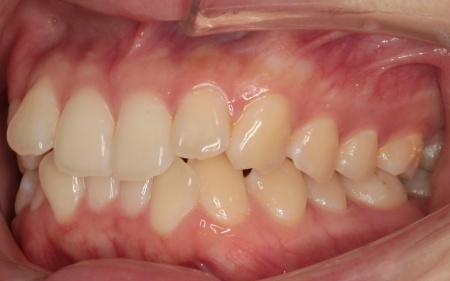

20代女性 乱れた上下の歯並びをハイブリッド矯正で改善した症例

拝見したところ、上下の歯はデコボコに生えている状態でした。

患者様は「できるだけ目立たない治療方法で、なるべく早く終わらせたい」と希望されていたため、ハイブリッド矯正を提案し、同意いただきました。

ハイブリッド矯正とは、ワイヤー矯正とマウスピース矯正の両方を行う方法です。先にワイヤー矯正で歯を大きく移動させたあと、マウスピース矯正で仕上げることで、治療期間の短縮が望めます。